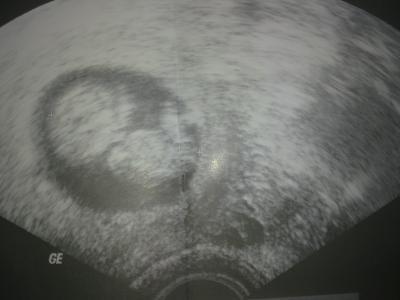

Guten Morgen Zusammen! Wisst Ihr schon was Ihr euren Mamiis zum Muttertag schenkt? Ich wollte eigentlich eine Foto-Torte machen lassen, aber meine Mama mag kein Marzipan und ich ehrlich gesagt auch nicht! Ich bin schon die ganze Zeit am schauen im Internet ob ich vll auf eine Idee komme, aber mir fällt im Moment nichts ein. Ist zwar noch eine Weile hin, aber je nach dem was ich mache braucht es ja auch seine Zeit! Und einfach Blumen und Pralinen kaufen möchte ich nicht. Vorletztes Jahr habe ich ihr ein Video erstellt, sie hat sich so darüber gefreut das sie ein paar Tränen vergossen hat. Das zum Beispiel hat über 1.Monat gedauert bis ich die passenden Bilder, Texte etc. zusammen, bearbeitet und in das Video gepackt hatte. Ich möchte Ihr gerne wieder so ein tolles Geschenk bereiten, aber weiß nicht genau was. Ich werde Ihr auf jeden Fall am Morgen ein tolles Frühstück bereiten, mit schöner Dekoration, Rosen, leckerem Frühstück und alles was so einen Tag schön Starten lässt. Wisst Ihr vielleicht eine Seite die solche Foto-Torten etc. auch ohne Marzipan machen können? Ich hoffe ihr könnt mir helfen. Wünsche Euch und eurem Krümmel noch eine wunder schöne Nacht. Nelly + Vanessa mit 10 Wochen und heute 4 Tagen Bild: Ultraschall aus der 9.SSW